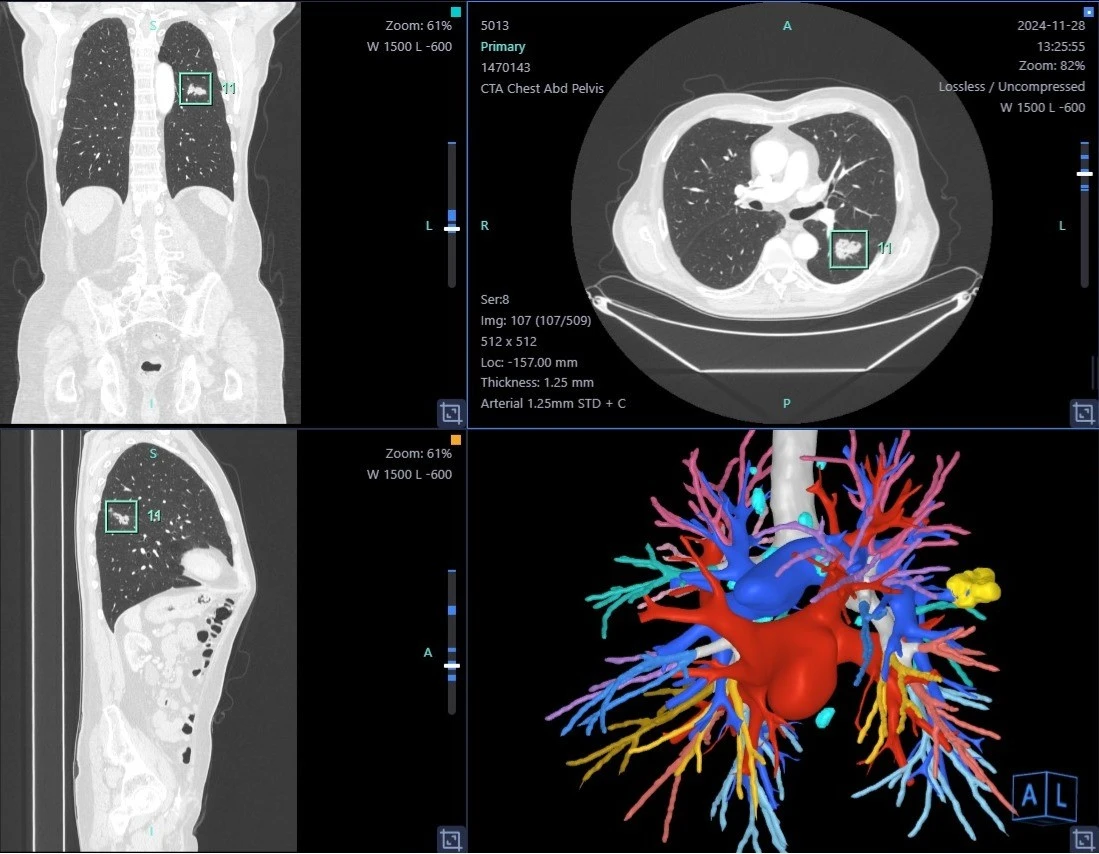

Εφόσον κριθεί και αποφασιστεί στα πλαίσια του Ογκολογικού Συμβουλίου ότι ο πνευμονικός όζος πρέπει να αφαιρεθεί εφαρμόζεται σε όλους ανεξαιρέτως τους ασθενείς η τεχνική 3D-LU.M.I.N.A. (3D - LUng Mapping with Icg and Navigation Assistance).

Η τεχνική εντοπισμού μονήρους πνευμονικού όζου με συνδυασμό τρισδιάστατης (3D) αξονικής απεικόνισης και έγχυσης ινδοκυανίνης (ICG – Indocyanine Green) είναι μια καινοτόμος και ιδιαίτερα αποτελεσματική προσέγγιση που εφαρμόζεται κυρίως σε ελάχιστα επεμβατικές θωρακοχειρουργικές τεχνικές.

1. Προσχεδιασμός με Τρισδιάστατη CT Απεικόνιση:

• Πραγματοποιείται υψηλής ανάλυσης αξονική τομογραφία θώρακος (CT).

• Τα δεδομένα ανασυντίθενται σε τρισδιάστατο μοντέλο των πνευμονικών δομών, περιλαμβάνοντας αγγεία, βρόγχους και τον όζο.

• Αυτό επιτρέπει τον ακριβή υπολογισμό της θέσης του όζου σε σχέση με ανατομικά ορόσημα (π.χ. αγγεία, λοβοί, βρογχοπνευμονικά τμήματα).

3. Συνδυασμός Δεδομένων σε Πραγματικό Χρόνο:

• Το προεγχειρητικό 3D μοντέλο "συγχωνεύεται" με την διεγχειρητική εικόνα (κάποιες φορές μέσω τεχνολογίας επαυξημένης πραγματικότητας - augmented reality ή λογισμικών πλοήγησης).

• Ο χειρουργός γνωρίζει με μεγάλη ακρίβεια πού βρίσκεται ο όζος ακόμα και αν είναι μη ψηλαφητός.

Η 3D-LUMINA που εφαρμόζεται αποκλειστικά στον Κυανού Σταυρό είναι μια υβριδική τεχνική απεικόνισης που συνδυάζει τρισδιάστατη ανασύνθεση πνευμονικών δομών με φθορίζουσα καθοδήγηση μέσω ινδοκυανίνης.